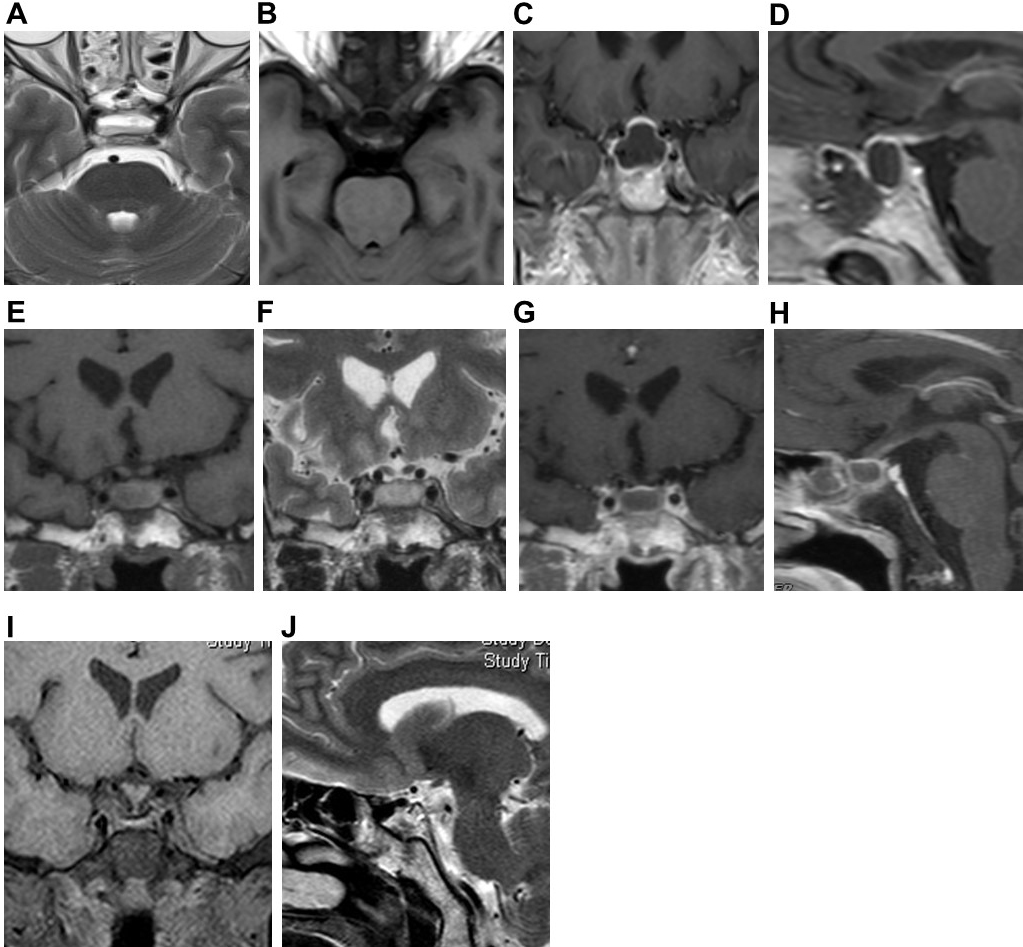

Fig. 3.

Fig. 3.Pituitary gland MRI of Case 3. Preoperative axial (A,B) MRI plain scans showed cystic lesions in the sellar region. T1WI showed uneven and slightly high signal, and T2WI showed a slightly high signal, with a fluid plane inside. Preoperative coronal (C) and sagittal (D) MRI enhanced scan showed ring enhancement of the cyst wall, thickened and enhanced pituitary stalk. Postoperative coronal (E,F) MRI plain scan showed cystic lesions in the sellar. T1WI showed a high signal, T2WI showed a slightly high signal. There was sphenoid Sinus mucosal thickening with effusion. Postoperative coronal (C) and sagittal (D) enhanced MRI scans showed ring enhancement of the capsule wall. Coronal (I) and sagittal (J) MRI plain scans after the second operation showed no recurrence of the pituitary abscess.

Fig. 4.

Fig. 4.Preoperative pituitary MRI, intraoperative image and postoperative CT of Case 4. Preoperative coronal (A), sagittal (B), and axial (C) MRI plain scans showed cystic lesions in the sellar region, low signal on T1WI, high signal on T2WI. The mucosa of the sphenoid sinus at the sellar floor was significantly thickened. Submucosal effusion was observed. Preoperative coronal (D) enhanced MRI scan showed partial enhancement of the cyst wall. During operation (E), the pus was yellow and viscous. Postoperative head CT (F) showed no recurrence of the pituitary abscess.